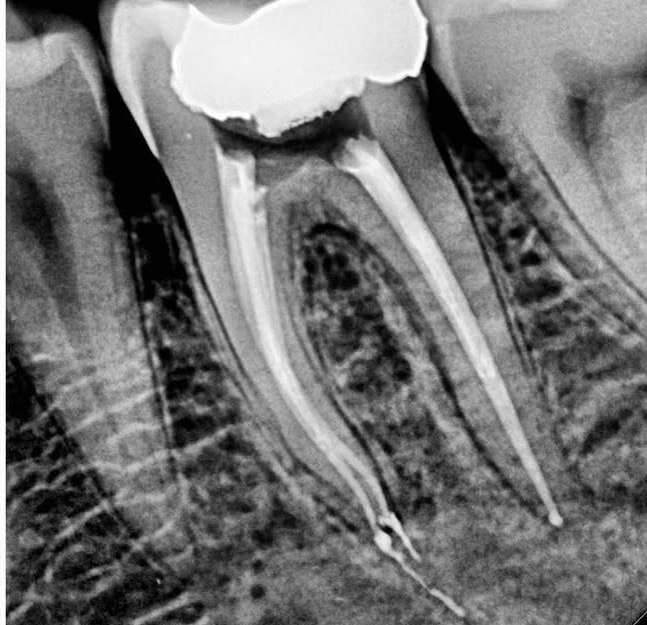

1. What Condition can be seen in this X ray regarding the tooth # 1.1.?